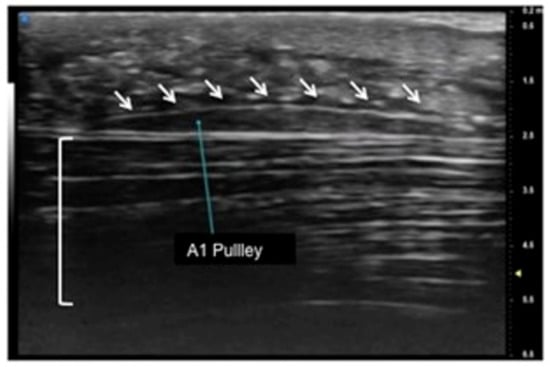

Figure 1.

Sagittal view of A1 pulley (white arrows) presenting as a fusiform structure with a hypo-echoic signal contoured by a thin hyperechoic line. The superficial flexor tendon is visible (square parenthesis).